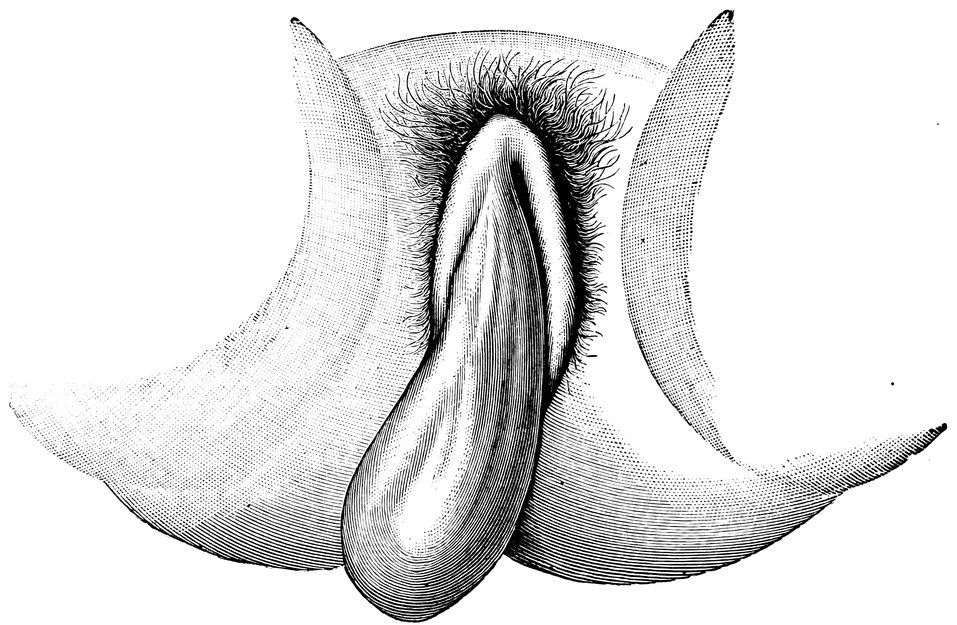

| 68. | “Hottentot Apron” in an adult Woman, hanging down between the thighs (after Zweifel) | 329 |

| 69. | Elephantiasis of the Labia Majora | 330 |